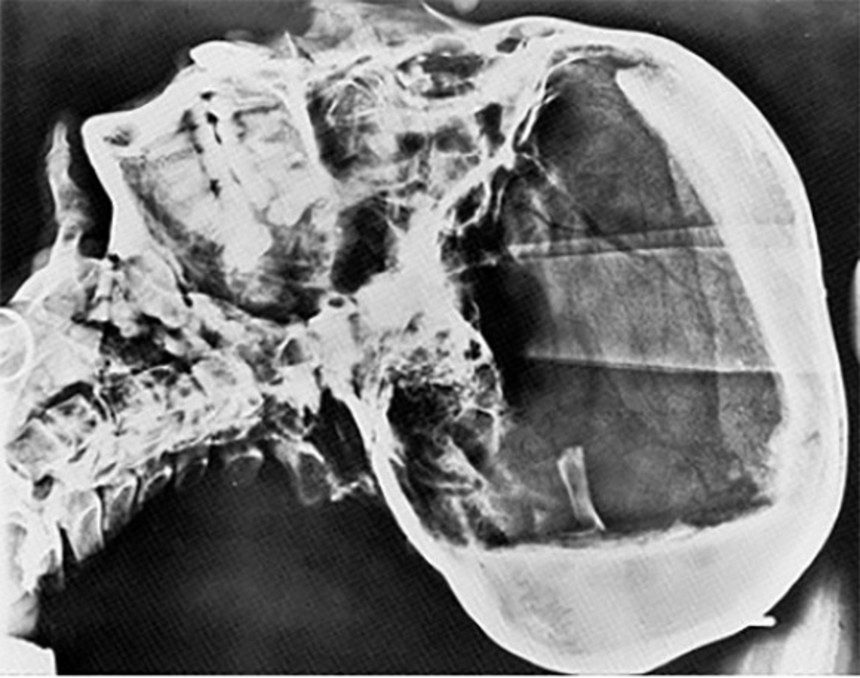

8. サー・アーチボルト・ダグラス・リード

この画像を大きなサイズで見るツタンカーメン王墓の発掘メンバーでなくても、呪いの犠牲になることを証明してしまった例。リードは放射線学者でツタンカーメン王のX線写真を撮って、博物館へ送っただけなのだが、翌日から体調を崩し、3日後に急死したという。